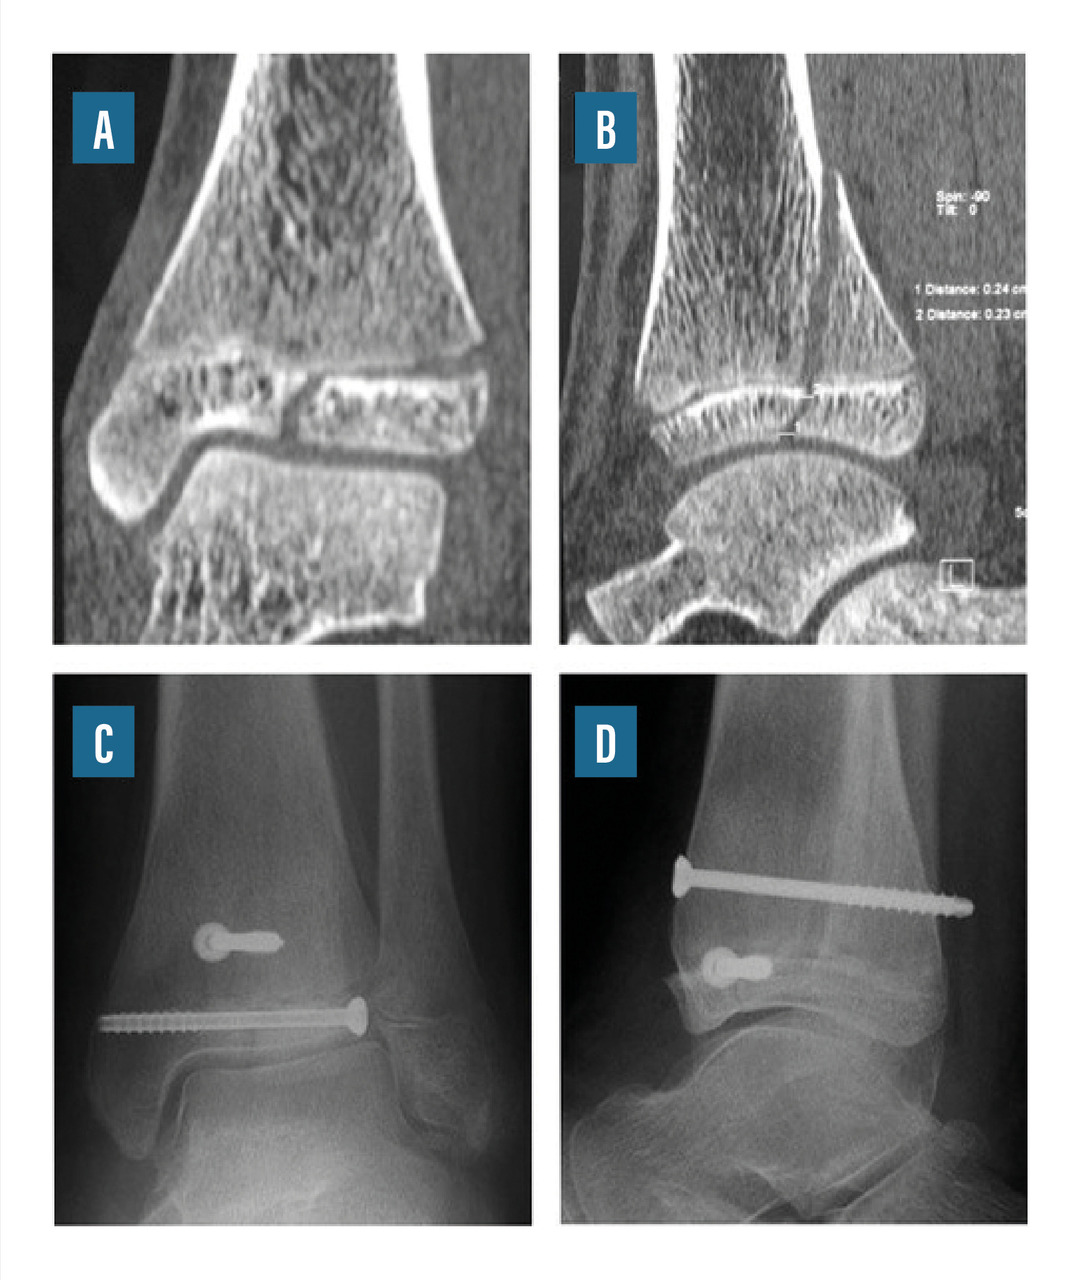

• le vissage percutané par vis canulée montée sur des broches (fig. 9) ;

Les fractures-décollements épiphysaires de type Salter III ou IV posent les problèmes spécifiques du trouble de croissance éventuel et des lésions d’arthrose articulaire à long terme. La fracture de Tillaux représente une forme particulière de fracture de type III : elle survient chez le grand enfant qui a déjà soudé une partie de la zone de croissance. Les fractures déplacées imposent une réduction parfaite, soit en technique percutanée sous contrôle radiologique, soit à foyer ouvert avec contrôle visuel.

La fracture de Mac Farland est une fracture de type Salter III ou IV consécutive à un mouvement d’adduction du pied. Elles peuvent survenir chez des enfants jeunes et ont, dans ce cas, un risque élevé de trouble de croissance et, à terme, de défaut d’axe de la cheville. Les fractures déplacées imposent une réduction parfaite, soit en technique percutanée sous contrôle radiologique, soit à foyer ouvert avec contrôle visuel.

Certaines fractures associent des traits de fracture dans trois plans de l’espace : ce sont les fractures « triplanes ». Leur traitement est le plus souvent chirurgical.